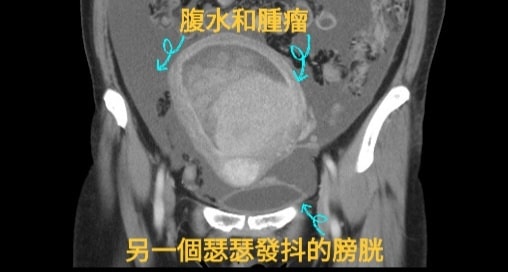

腹脹兩個星期揭患骨盆腔腫瘤

其二,另一位已經停經的5旬婦女因在兩個星期裡一直感到腹脹與消化不良,就算看診了也毫無進展。直到來到醫院檢查,經過電腦斷層掃描後,才發現有個巨大的骨盆腔腫瘤,且再加上轉移導致腹水的情況出現。對此,戴醫生表示,面臨這些突如其來的疾病,「醫生也是人,會有同情心,也會驚,也會慌。」